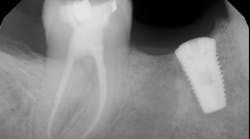

Once all of the canals are found, I will go through the series of Sybron Twisted Files size 25 tapering from 0.10 to 0.80 to 0.60 to 0.40. The 0.40 file should reach the working length for most canals. On a large palatal or distal canal, the 0.60 TF will usually reach working length. After which, using the crown-down technique with the Brasseler EndoSequence rotary files, instrument each canal until files reach the working length. Once instrumentation is complete, take a P.A. with gutta-percha to confirm instrumentation to working length. I find it much easier to take working length films with gutta-percha rather than files (which may fall out, bend, or separate)